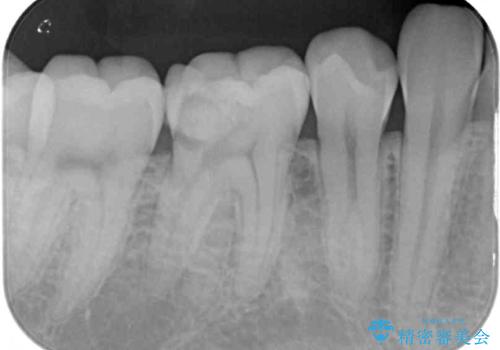

- 下顎左右奥歯に虫歯で痛みを感じるとのことで来院された患者様です。

むし歯が大きく、神経を取り除く可能性があることを理解いただいた上で虫歯を取り除き、その後はオールセラミッククラウンにて補綴することとしました。

虫歯除去後に痛みは収まり、神経も保存することができました。